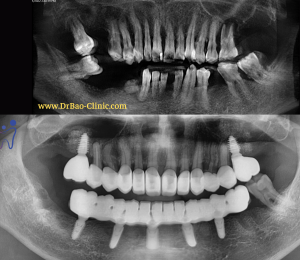

1/ Tình trạng ban đầu:

Giai đoạn 1: nhổ răng nhiễm trùng + đặt 7 trụ implant có ghép xương

Panorama Xray after 1st surgery

Panorama Xray after 3rd surgery

Phim tái khám sau 3 tháng mang phục hình sau cùng